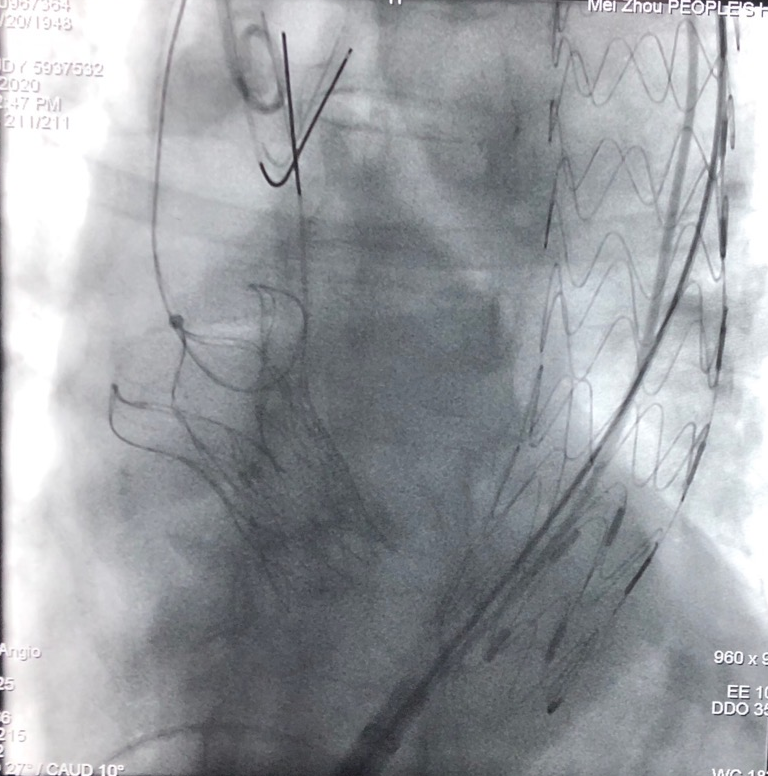

针对这位患者的特殊病情,在术前的多学科会诊中,我院结构性心脏病学组的钟炜教授首次提出“一站三式”的手术方案,即经颈动脉主动脉瓣置换术(TAVR)联合胸主动脉腔内修复术(TEVAR)联合经皮球囊主动脉缩窄血管成形术(PBACA)同步开展。

术前,梅州市人民医院心血管病中心团队在钟志雄教授带领下对术中各项风险进行了全面评估,对TAVR、TEVAR以及PBACA的先后顺序和各个步骤进行了充分探讨,确保手术安全。在整个手术过程中,结构性心脏病学组的钟炜教授团队与外周血管病学组的李存仁教授团队默契配合,凭借精湛的技术和临危不乱的气度,历经8小时,克服了种种困难,手术取得圆满成功。

“一站式”手术完成